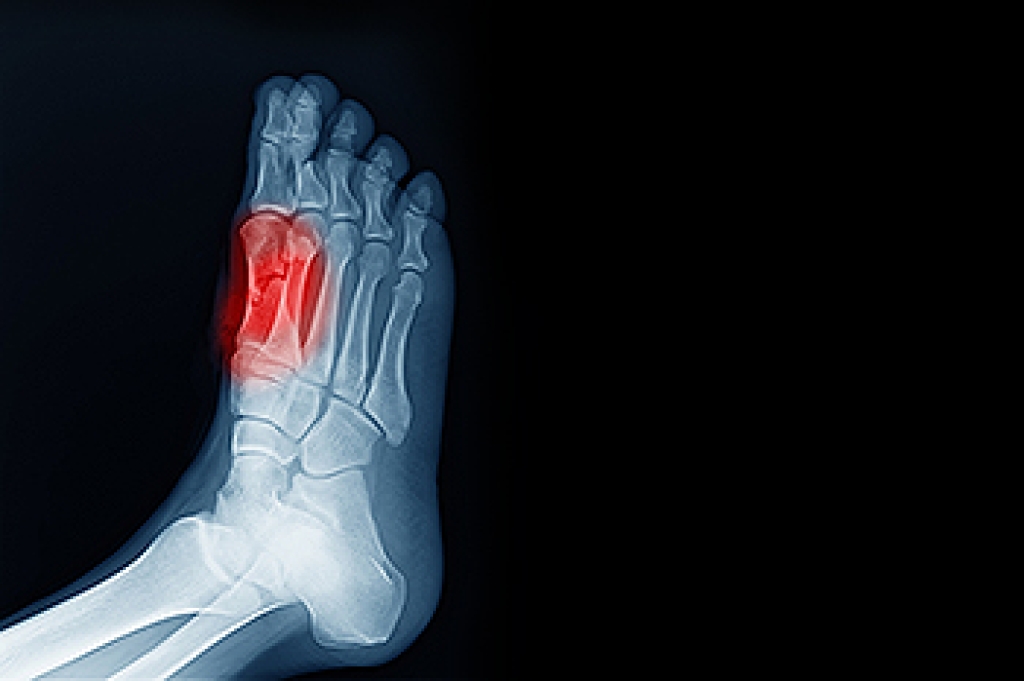

- Foot sores – amongst the older population can be serious before they are discovered. Some of the problematic conditions they may face are:

- Shoes that don’t fit properly

- Pressure sores

- Loss of circulation in legs & feet

- Edema & swelling of feet and ankles

Diabetes and poor circulation can cause general loss of sensitivity over the years, turning a simple cut into a serious issue.